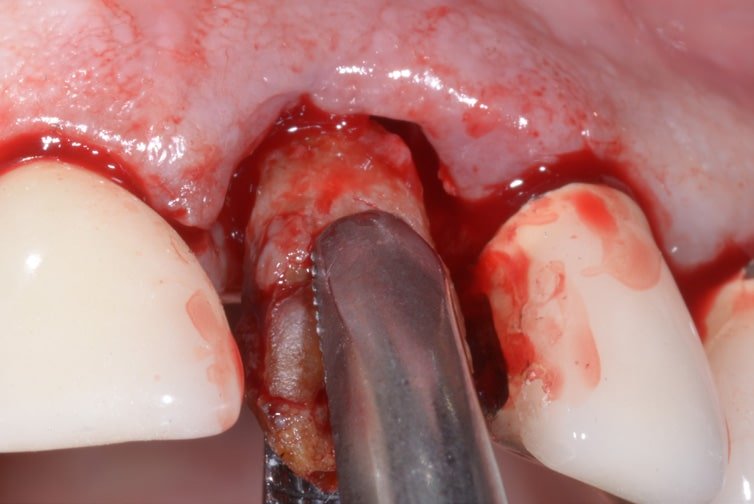

Use Of T-barrier Titanium Membrane And Regenerative Materials In Frontal Site

Dr. LUTFI UJAM Country: Sweden Gallery Patient’s Data: Age: 40 Sex: Male Smoker: Yes Pathologies: High blood pressure Hygenic state: Fair Alergies: None This patient have had an extraction of a central incisor and wants to restrore the aesthetic of his smile. The insertion of a 3P implant has been made with a fully open […]